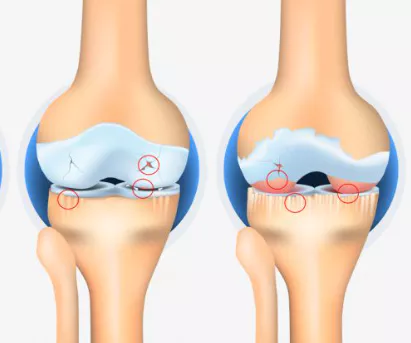

무릎 관절염은 많은 사람들에게 영향을 미치는 흔한 관절 문제 중 하나입니다. 이러한 질환이 있는 환자들은 적절한 운동을 통해 무릎 관절을 더욱 강화하고 통증을 완화하는데 도움을 줄 수 있습니다. 이 글에서는 무릎 관절염에 좋은 운동 10가지 및 주의사항에 대해서 자세히 살펴보겠습니다.